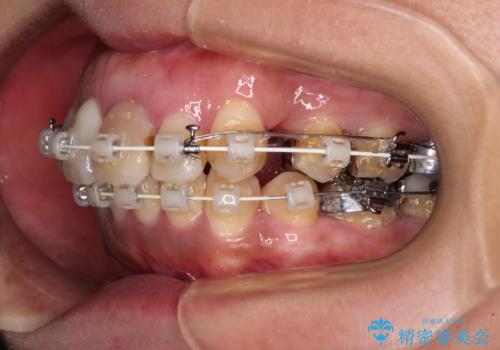

- 矯正装置

- 審美装置

- 歯列全体が内側に倒れ込んでいることと、口元の突出感を気にして来院された患者様です。

上下ともに歯列が狭窄しており、前方に突出している状態でした。

歯が重なるような叢生も認められたため、上下左右の第一小臼歯4本を抜歯して、口元が引っ込むように治療を行うこととしました。